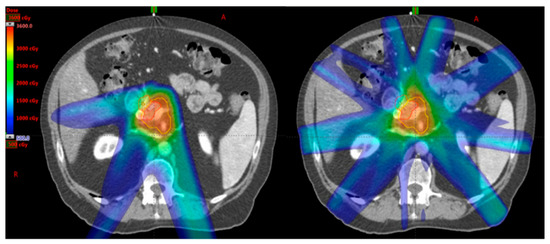

The proton beam, a particle therapy, has the benefit of delivering dose to the target with no exit dose in the beam path (Figure 2); thereby potentially reducing dose to the normal tissues within the exit beam path [25]. This, theoretically, may reduce both acute and late toxicities of treatment. In addition, with minimal dose in the exit beam path, proton therapy opens the door to possible dose escalation studies. As proton therapy is a relatively new player in the clinical radiation oncology domain, the evidence for the use in pancreatic cancer remains limited. Table 3 summarizes the current literature for particle therapy in pancreatic cancer.

Figure 2.

An example of proton (Left) and photon (Right) SBRT plans on the same patient. Note that there is less low dose scatter in the proton plan due to the inherent physical properties of proton particles compared to photon.

A dosimetric study comparing IMRT and proton plans in 13 patients with unresectable pancreatic cancer, planned to 55 Gy in 25 fractions, by Thompson et al. [26] demonstrated that proton plans, utilizing either passive scattering or pencil beam scanning, yielded significantly lower doses to the stomach, duodenum and small bowel in the intermediate to low dose regions (defined as volume receiving at least 20 Gy) compared to IMRT. However, in the intermediate to high dose regions (defined as volume receiving at least 45 Gy), proton plans had significantly higher dose to those structures compared to IMRT. However, proton plans did yield significant reduction in mean liver (50% reduction) and kidney (18% reduction) doses. The biological significance of reduced dose to the low dose regions remained to be investigated.

As proton is a charged particle, it has a higher linear energy transfer [27]. Therefore, proton therapy can potentially deliver higher relative biological effectiveness than photon therapy [27]. In theory, proton therapy could result in greater cell killing than photon therapy given the same dose/fractionation. Although this is a desirable effect on cancer cells, this may also indicate that greater care is required when delivering proton therapy as a small increase in dose to normal structures could potentially translate to greater risk of late toxicity compared to photon therapy. The exact ‘conversion’ of proton therapy dose effect to photon therapy equivalence remained under investigation. As image guidance in proton therapy is being developed and implemented, careful planning and motion management should be taken when delivering proton therapy to a moving target such as the pancreas.